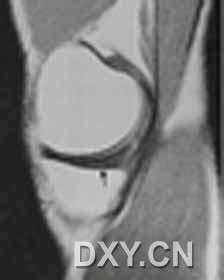

| 半月板体部放射状撕裂(体部垂直方向的高信号影)